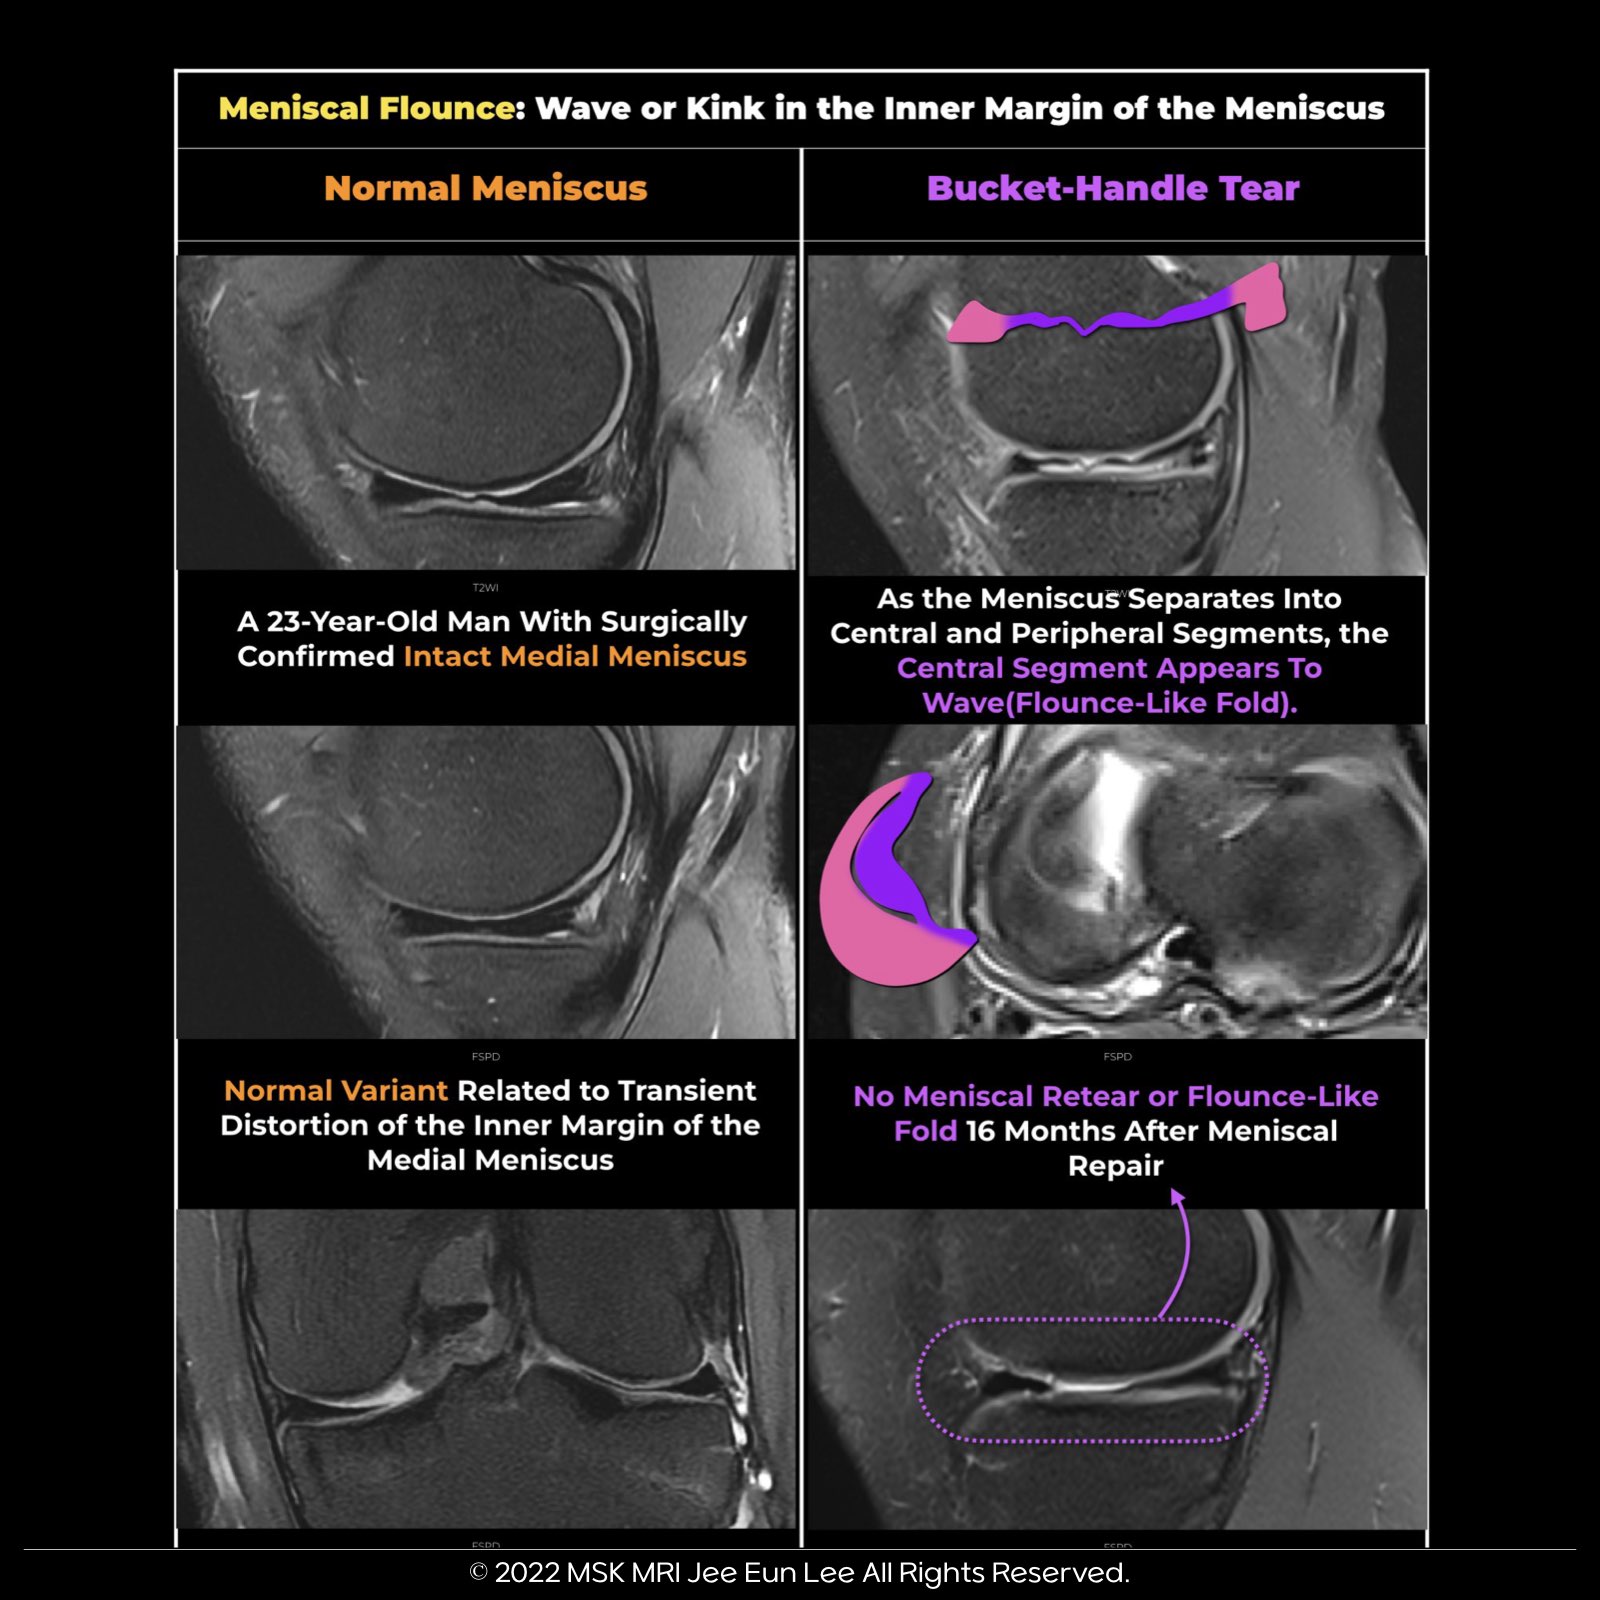

✅ Meniscal Flounce Summary:

- Meniscal flounce refers to a wave-like appearance of meniscus edges in sagittal MRI images.

- It occurs in about 0.2% to 0.3% of patients, mainly when the knee is flexed, and the free edge shows redundancy.

- While discussed in the context of the medial meniscus, it can also affect the lateral meniscus.

- The wave-like appearance is notable, but other attachments are usually intact, and no tearing is seen in coronal images.

✅ Pitfall:

- Flounce may mimic a torn meniscus in sagittal images but is not indicative of an actual tear.

- Coronal images can make the free edge look torn due to the wave-like shape.

✅ Don't Dismiss Flounce:

- When a meniscal flounce is detected, it's crucial to examine for potential ligamentous or capsular injuries that might cause laxity.

- Detecting a meniscal flounce necessitates checking for possible ligamentous or capsular injuries causing laxity, particularly with lateral meniscal flounces.

- These are rare and might suggest popliteomeniscal fascicle injury/deficiency, resulting in meniscal hypermobility.